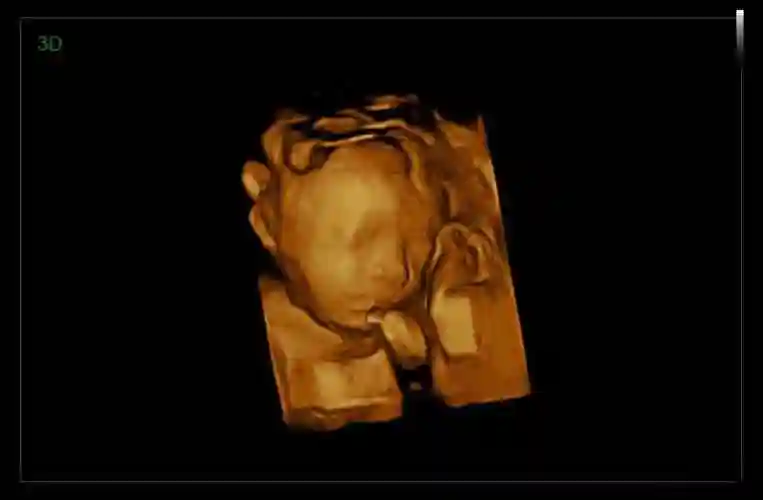

四维彩超看男女这么简单, 学到了

区别图一般来说,怀孕到了四个月的时候,胎儿的生殖器官已经开始发育了